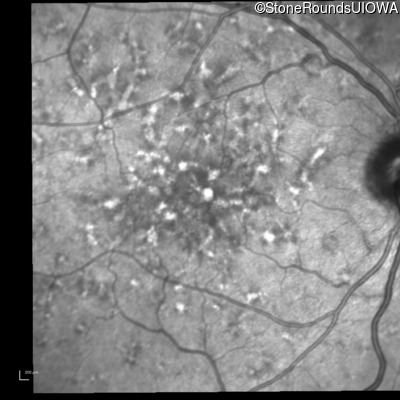

Fluorescein Angiography - Right - 20/40 +2 sc

Exemplar

Fluorescein Angiography - Left - 20/40 +1 sc